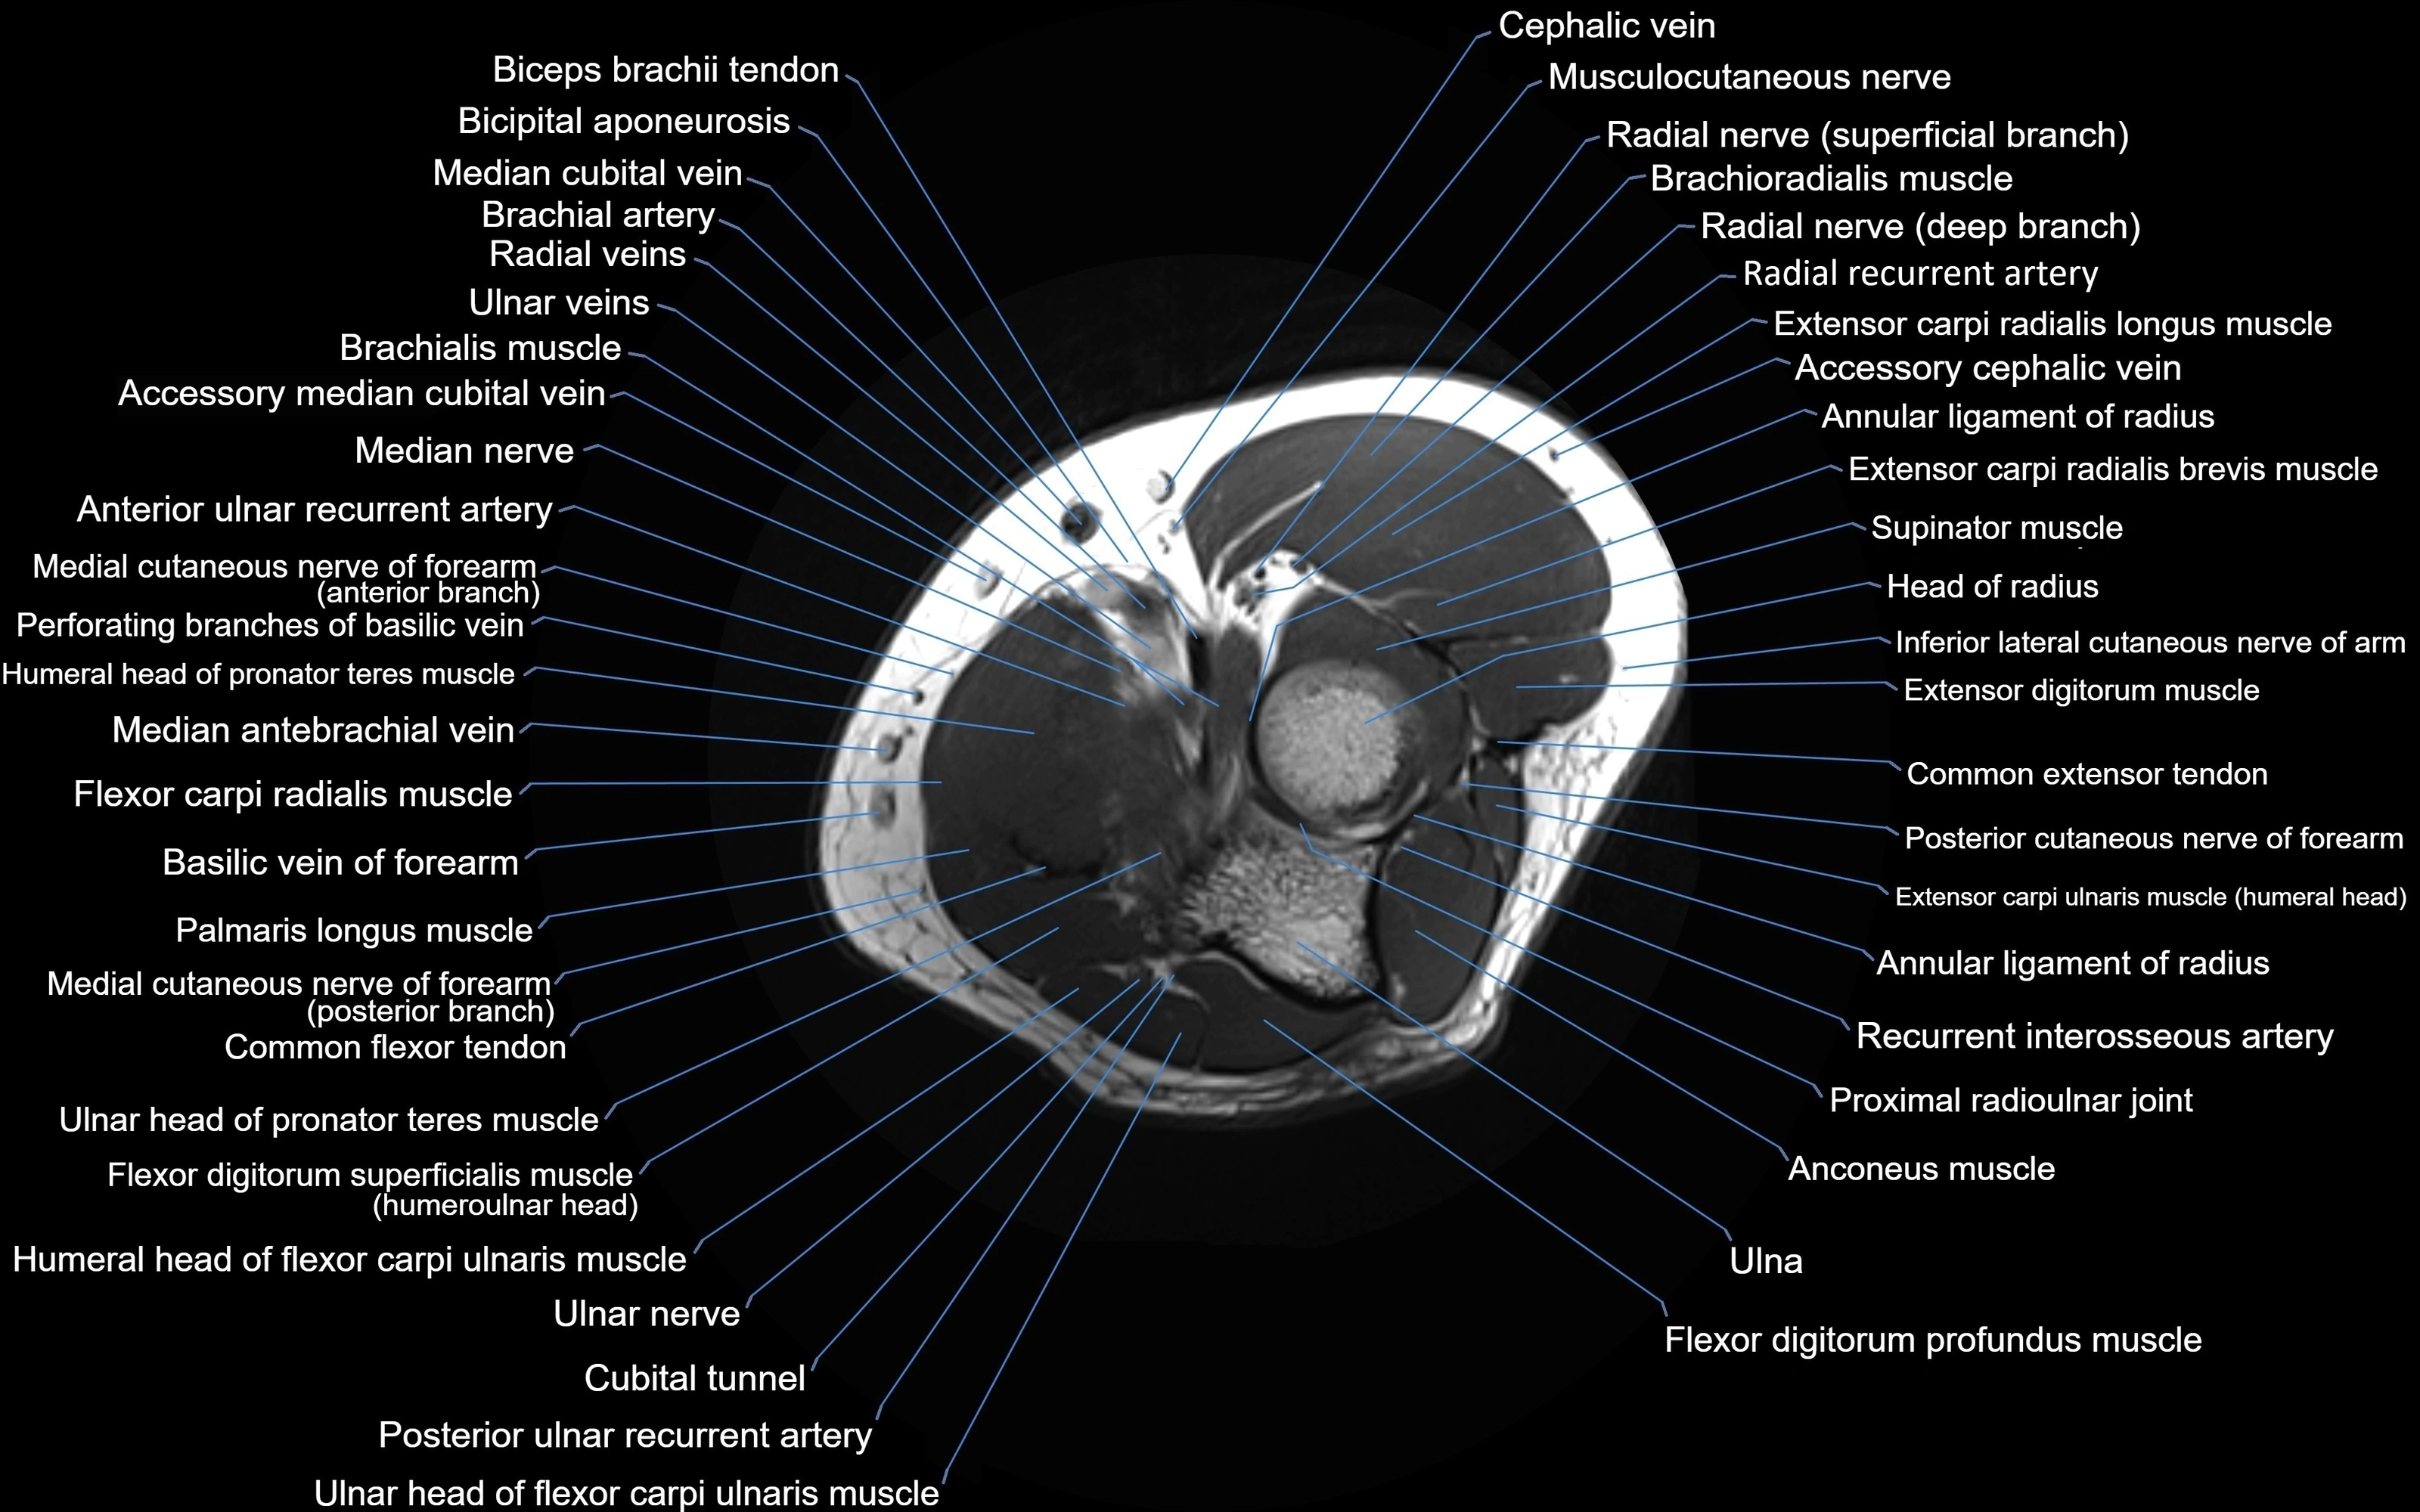

MRI image

image